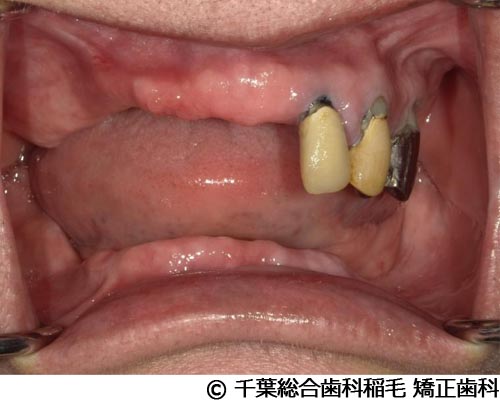

【症例3】上下5本インプラント埋入手術

- 治療前

- 治療後

- 治療名

- 上下5本インプラント埋入手術

- 費用

- 2,500,000円(税込)

- 期間

- 11ヵ月

治療内容

-

患者様の症状

欠損歯が多いため、お食事が取りにくく、インプラント治療のご相談でご来院されました。

治療法

状態の悪かった歯も含め、上下5本インプラントを埋入しました。

治療結果

奥歯でしっかり噛めるようになったと喜んでいただけました。

現在も定期健診で拝見させていただいています。

※治療結果は患者様によって個人差があります。